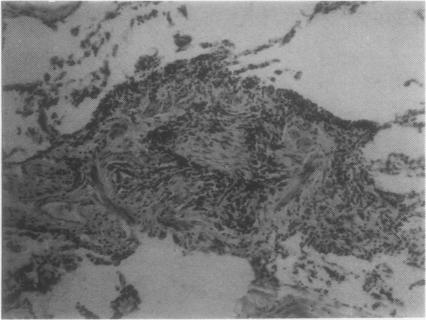

Among 173 consecutive open lung biopsies, nine gave a histopathological diagnosis of bronchiolitis. Seven of these patients had some connective tissue disorder (CTD), six of whom are presented in this report; two had classical and one possible rheumatoid arthritis (RA), one ankylosing spondylitis, one scleroderma, and one developed classical RA four years after biopsy. Four of the patients were smokers, most suffered from breathlessness and cough. In terms of lung function three patients had obstruction, one both restriction and obstruction and three a decreased diffusion capacity. For control purposes peripheral lung tissue was studied histologically from 24 consecutive smoking patients without CTD who underwent a lobectomy for cancer. Intraluminal plugs and mucosal lymphoplasmocytic infiltration of the bronchiolar walls were more prevalent and abundant in the CTD patients than in the controls (p less than 0.02 and p less than 0.001 respectively). Two CTD patients also showed some obliterative bronchiolitis. Corticosteroids were effective in one out of four patients treated. One patient improved and the others did not show any progression during the follow up. The results suggest that smoking alone does not explain the lesions of the small airways found in CTD patients, and that bronchiolitis may be specifically associated with the basic disorder in such cases.

在173例连续的开胸肺活检中,9例组织病理学诊断为细支气管炎。其中7例患者患有某种结缔组织病(CTD),本报告介绍了其中6例;2例患有典型类风湿关节炎(RA),1例可能患有RA,1例强直性脊柱炎,1例硬皮病,1例在活检后四年发展为典型RA。4例患者吸烟,多数有气促和咳嗽症状。肺功能方面,3例有阻塞性病变,1例有阻塞性和限制性病变,3例弥散功能降低。为作对照,对24例连续的因癌症接受肺叶切除术、无CTD的吸烟患者的外周肺组织进行了组织学研究。与对照组相比,CTD患者的细支气管腔内栓子和支气管壁黏膜淋巴细胞浸润更为普遍且更明显(分别为p<0.02和p<0.001)。2例CTD患者也显示有闭塞性细支气管炎。4例接受治疗的患者中1例对皮质类固醇有效。1例患者病情改善,其他患者在随访期间无病情进展。结果表明,单纯吸烟不能解释CTD患者中发现的小气道病变,在这些病例中细支气管炎可能与基础疾病有特定关联。